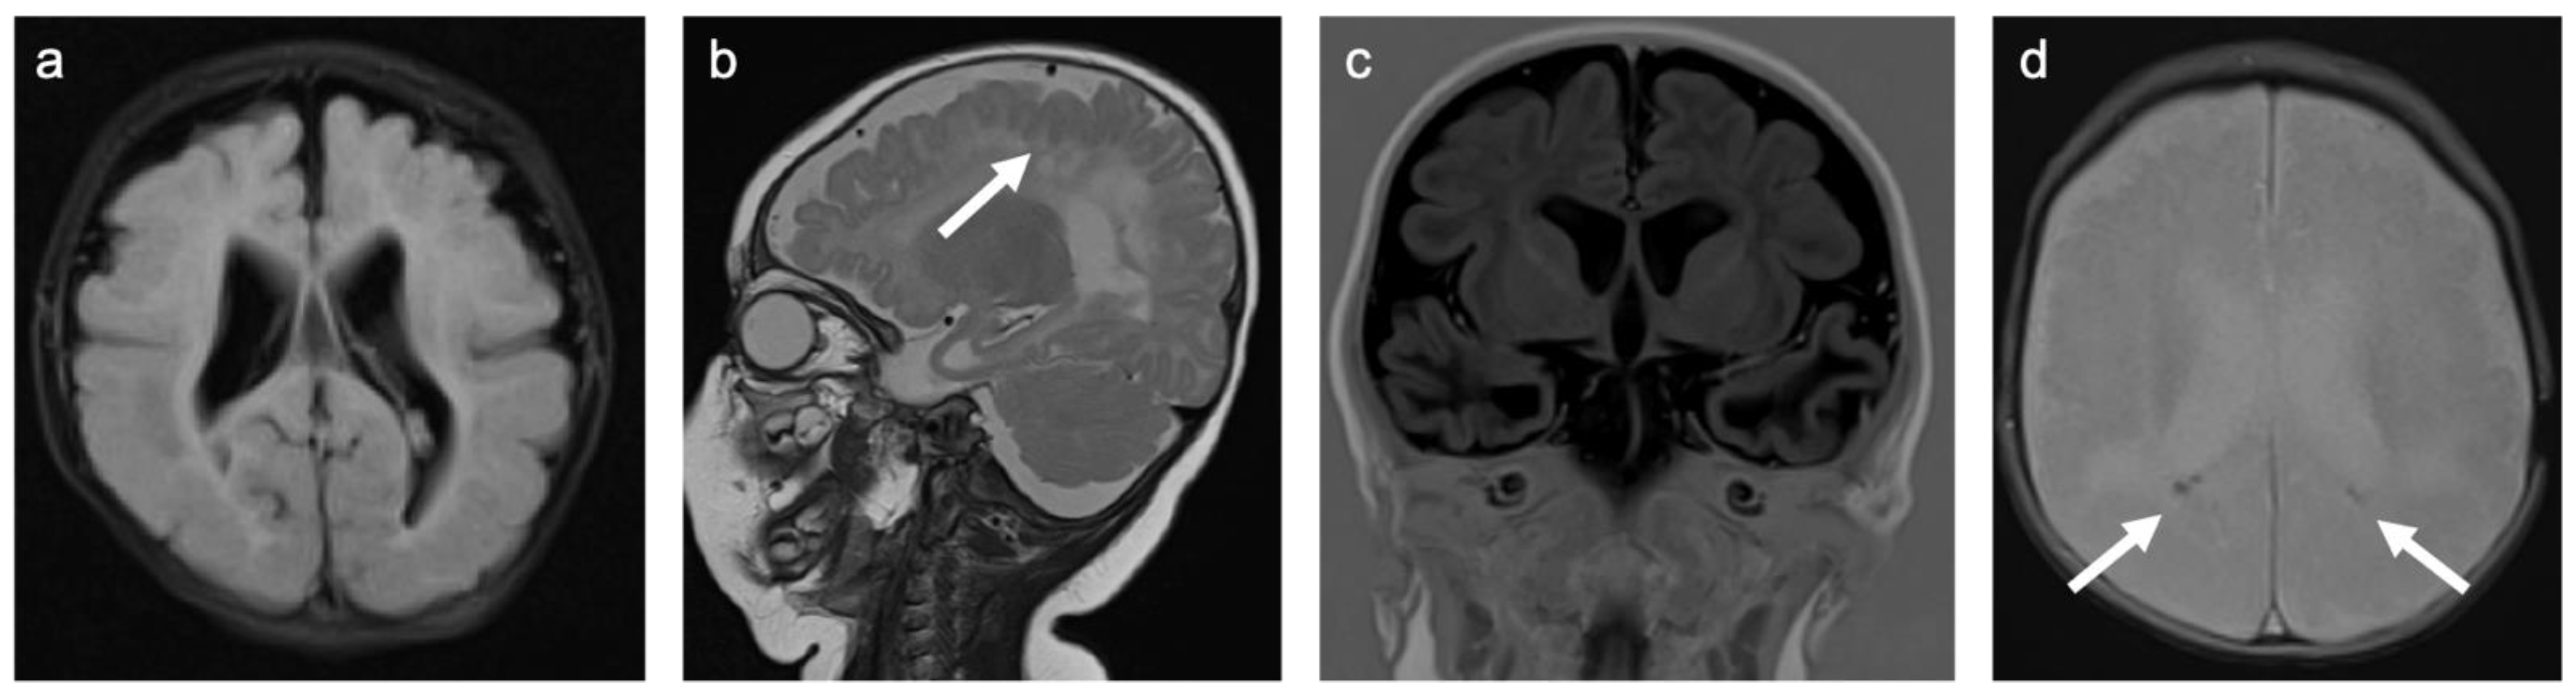

There were only two patients in Group 3. One patient had a history of traumatic brain injury at the age of 1.5 years, the other patient was admitted after a traumatic car accident. A representative case is shown in Figure 5. Both patients were female. They were 7 and 14.5 years old. One patient was examined with contrast-enhanced MRI. None of the examinations showed enhancing lesions. WMSAs in this group of patients were localized supratentorial only. Both patients had multifocal WMSAs.

Figure 5. Representative case “Traumatic white matter injuries”: diffuse axonal injury. DWI/ADC (a,b), T2W (c), and Susceptibility weighted imaging (SWI; (d)) sequences. Fourteen-year-old girl admitted after a traumatic car accident during which she was ejected from her seat. MRI shows a diffusion restricted, diffuse axonal injury lesion in the lobar white matter ((ac), white arrow). SWI demonstrates small regions of susceptibility artefacts at the grey–white matter junction corresponding to cerebral microbleeds (d). Additional findings are a subgaleal fluid collection (left side) following craniotomy for treatment of cranial impression fracture.